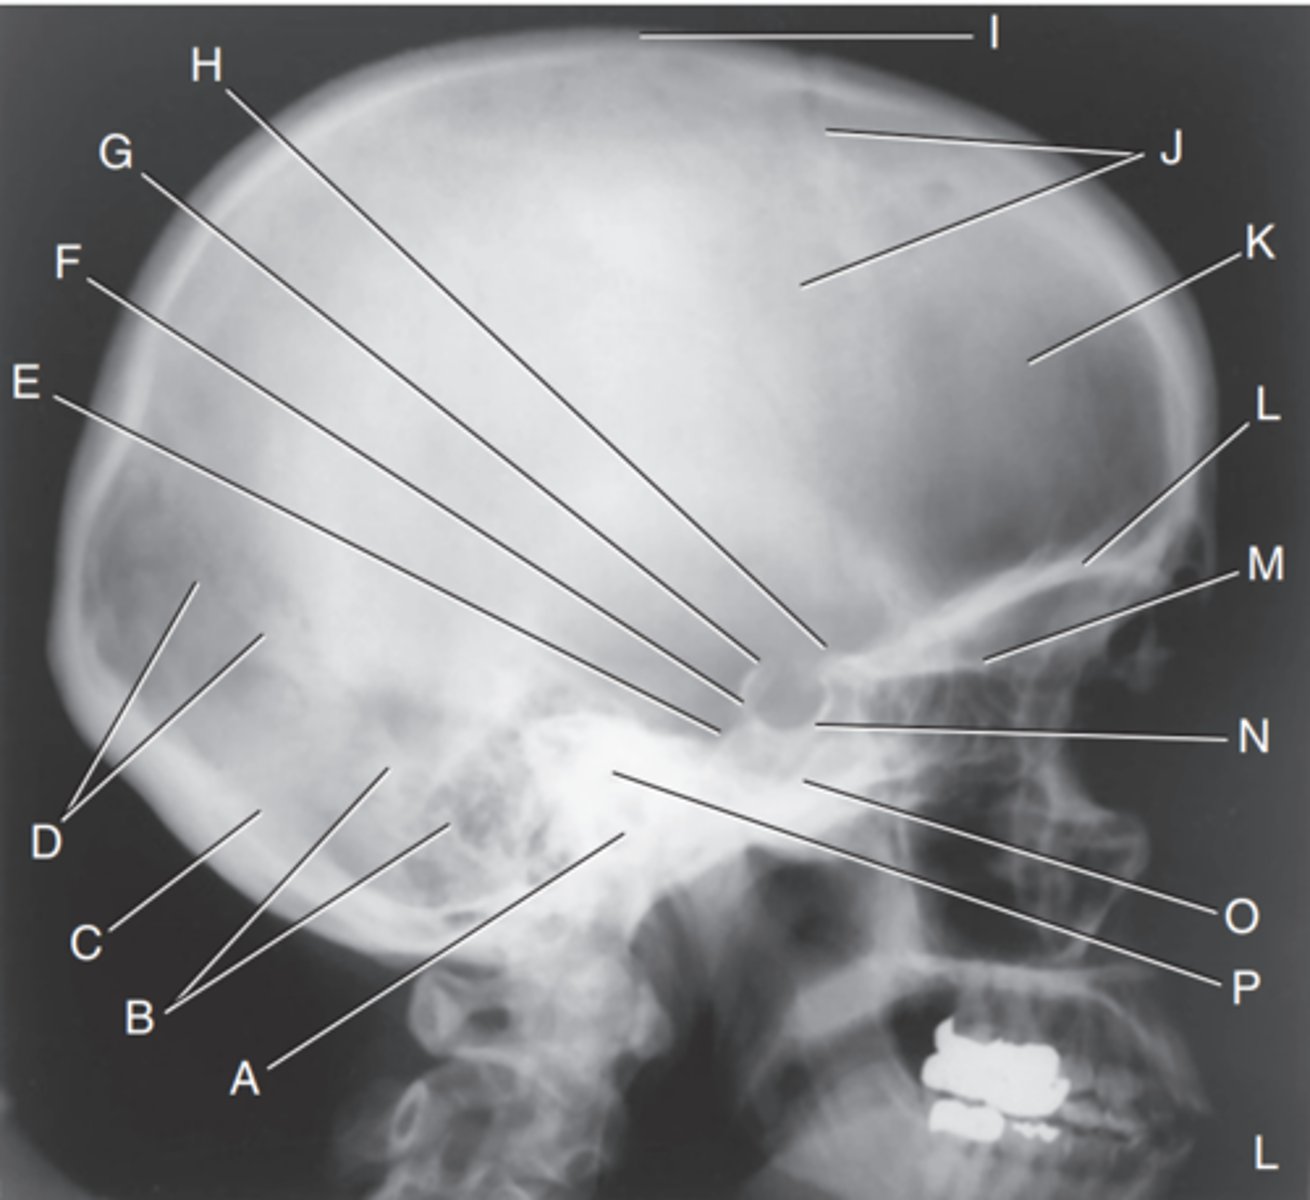

EAM

Label A

Mastoid portion of temporal bone

Label B

Occipital bone

Label C

Lambdoidal suture

Label D

Clivus

Label E

Dorsum sellae

Label F

Posterior clinoid processes

Label G

Anterior clinoid processes

Label H

Vertex of cranium

Label I

Coronal suture

Label J

Frontal bone

Label K

Orbital plates

label L

Cribriform plate

Label M

Sella turcica

Label N

Body of sphenoid (sphenoid sinus)

Label O

Petrous portion of temporal bone

Label P